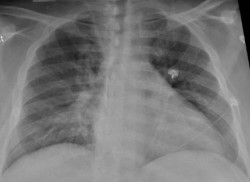

Un estudio revela un nuevo mecanismo de regeneración del tejido pulmonar

Una nueva investigación realizada en modelos de ratón por la Escuela Perelman de Medicina (Penn Medicine), de la Universidad de Pensilvania, en Estados Unidos, muestra, desde el punto de vista mecánico, cómo el pulmón infantil regenera las células después de una lesión de forma diferente al pulmón adulto. Los resultados de este estudio, publicados en `Cell Stem Cell`, demuestran que la suposición que se ha mantenido durante mucho tiempo de que las células AT1 y AT2 se comportan de la misma manera en los niños y en los adultos es falsa.